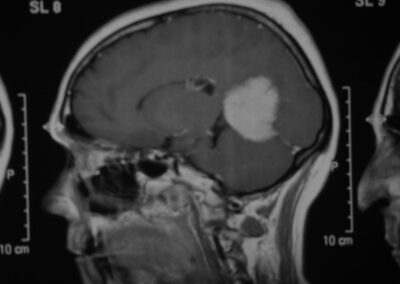

El diagnóstico se puede confirmar y el tumor localizar mediante:

• TAC cerebral

• RM cerebral